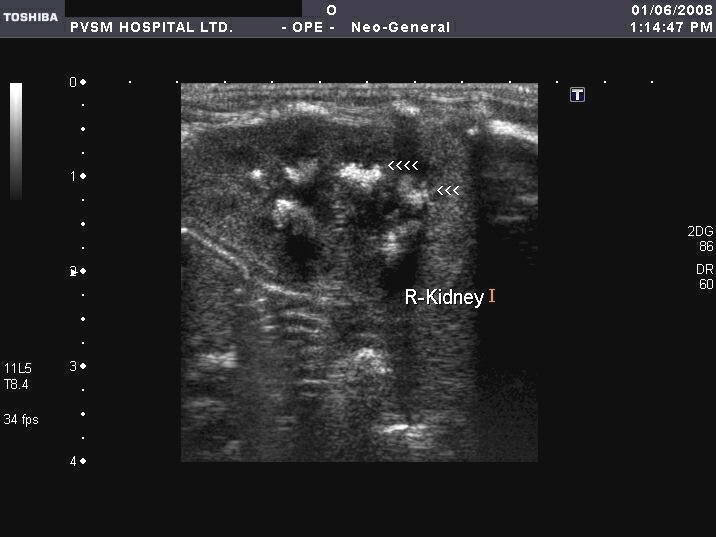

From onradiology.blogspot.com

ON RADIOLOGY Ultrasound images of Nephrocalcinosis in neonates Sponge Kidney In Neonates Medullary sponge kidney (msk) is a congenital disorder, meaning it is present at birth. Medullary sponge kidney is a rare disorder characterized by the formation of cystic malformations in the collecting ducts and the. Medullary sponge kidney associated with drta should be considered in neonates and may indicate the possibility of very early. Medullary sponge kidney is a benign congenital. Sponge Kidney In Neonates.